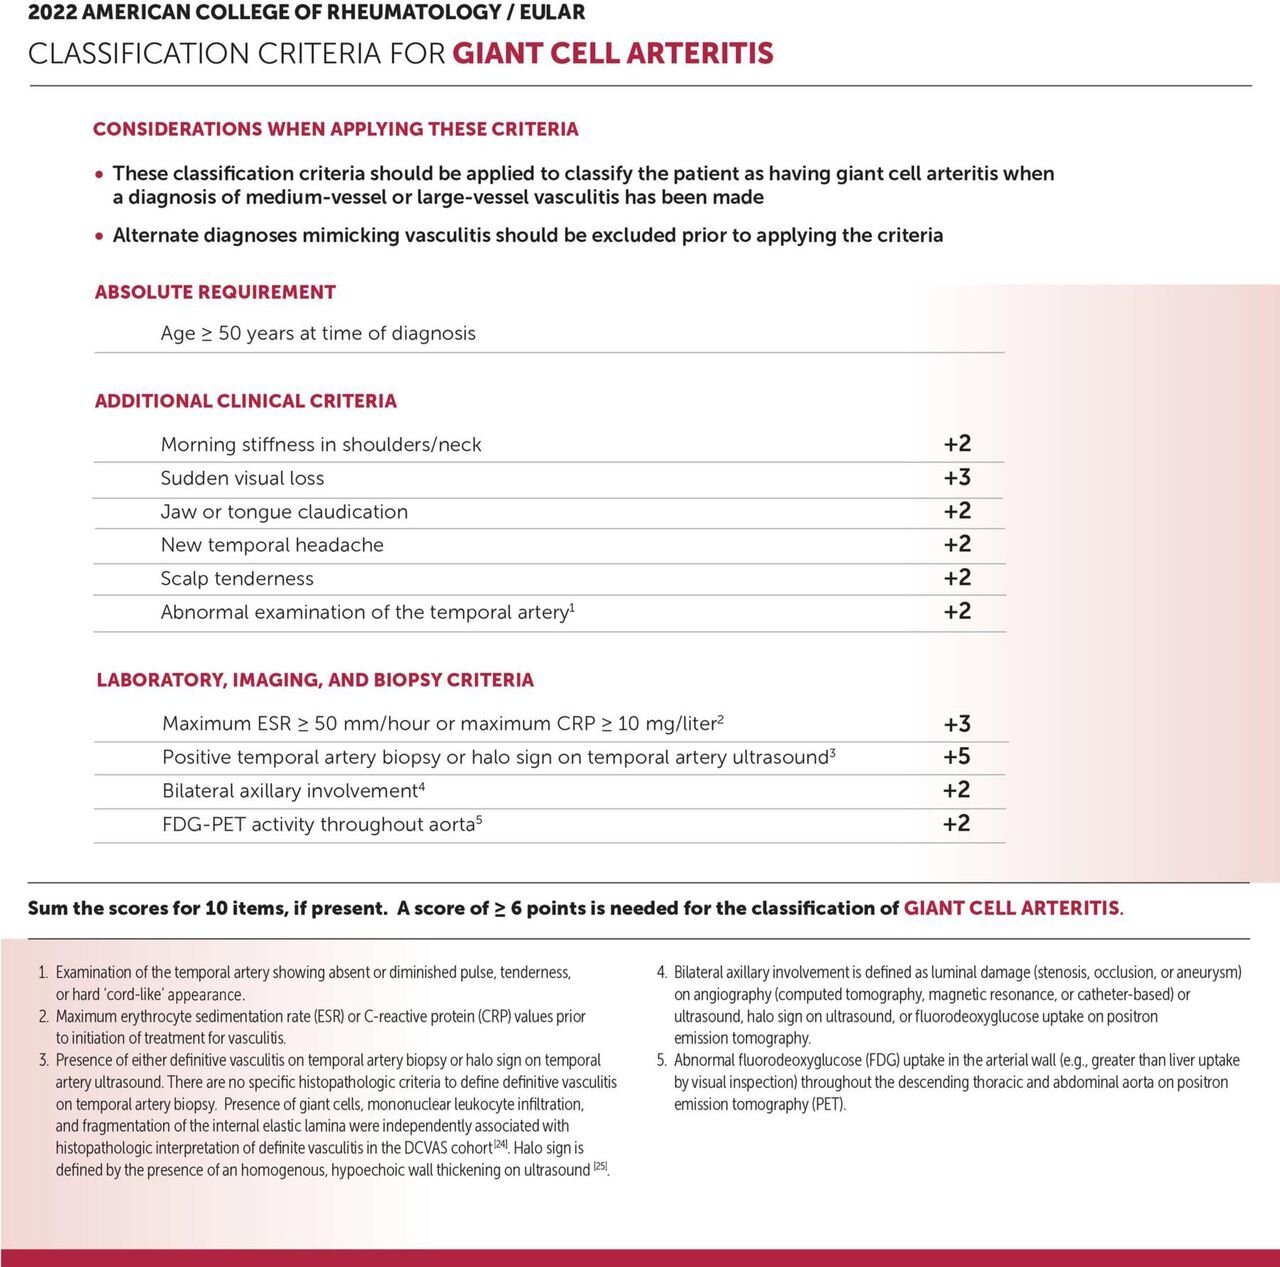

Updated Giant Cell Arteritis Classification Criteria